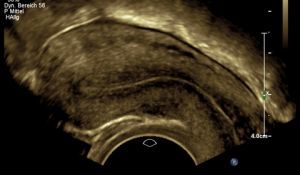

Aufgrund der Vielfalt an möglichen Symptomen handelt es sich in der Differentialdiagnostik um ein Chamäleon. Insbesondere die Manifestation innerhalb des Eierstocks (Endometriome, Schokoladenzysten) oder innerhalb der Gebärmuttermuskulatur  weisen ein charakteristisches Ultraschallbild auf. Daher ist die Vaginalsonographie ein wichtiger Bestandteil der Diagnostik zur Erkennung der Endometriose.

Adenomyosis

Die Endometriose ist eine Erkrankung, die durch Auftreten von Gebärmutterschleimhaut-ähnlichem Gewebe außerhalb der Gebärmutterhöhle  geprägt ist. Das abnorm lokalisierte Gewebe kann ein Vielfalt an Symptomen auslösen. Von zyklusabhängigen Schmerzen, Blutungsunregelmäßigkeiten bis hin zum unerfüllten Kinderwunsch können diese Probleme reichen.